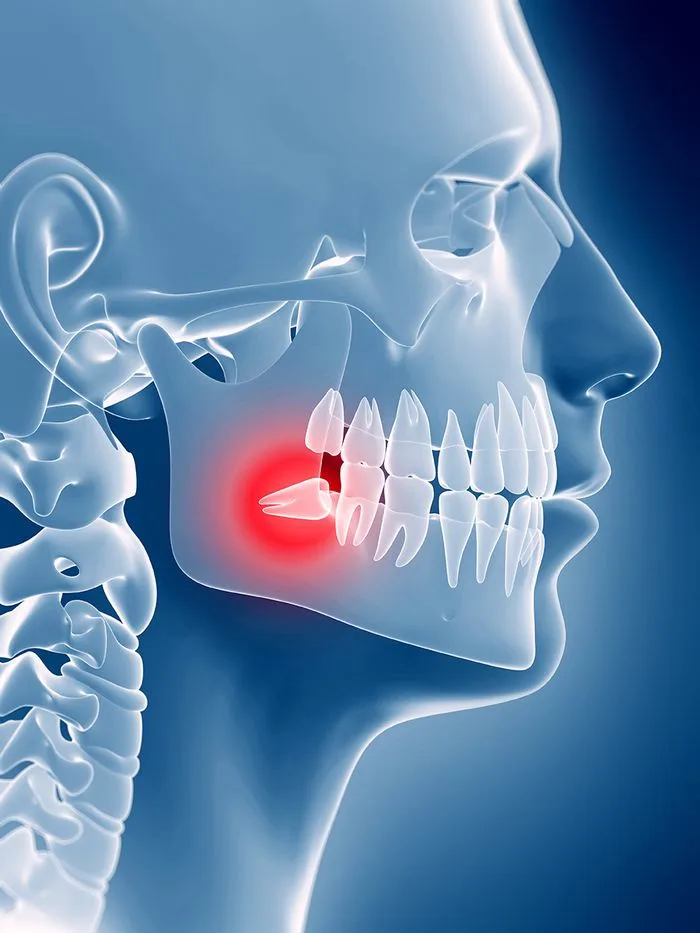

Sometimes a tooth causes more harm than good. While our top priority is to preserve your natural teeth, issues like severe decay, infection, or impaction can put your overall oral health at risk.

Wisdom teeth are often extracted if they’re impacted, causing pain, or crowding surrounding teeth. Your dentist will always explore all options before recommending removal, but sometimes extraction is the best way to protect your long-term oral health.